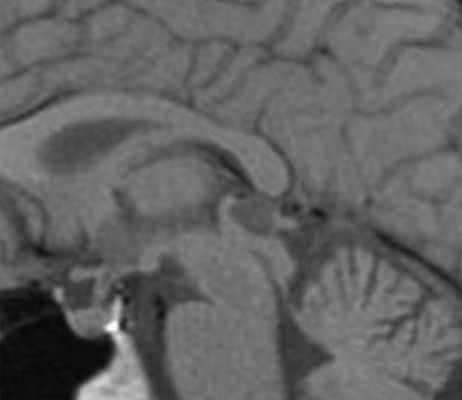

Пинеальная киста расположена в проекции шишковидной железы. Встречается с частотой 4-11%. Размеры обычно не превышают 1 см, но изредка встречаются больших размеров. В таких случаях она вызывает окклюзионную гидроцефалию. При МРТ головного мозга она имеет все признаки кисты с примесью белка в жидкости, то есть немного светлая на Т1-зависимых МРТ. Изредка встречается геморрагическое содержимое. Киста может по усиливаться периферии при МРТ головного мозга с контрастированием.

![Pineal cyst]()

МРТ головного мозга. Т1-взвешенная сагиттальная МРТ. Пинеальная киста.